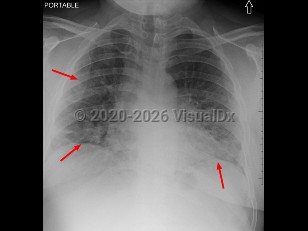

Aspiration pneumonia